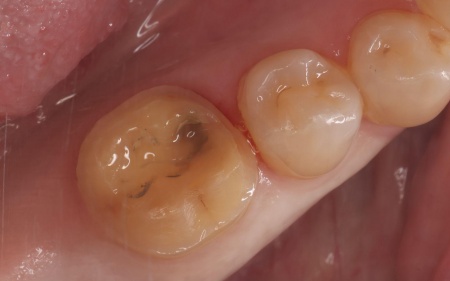

60代女性 欠けた奥歯を強度に優れたジルコニアのオンレーで修復した症例

拝見したところ、右下奥歯の一部が欠けている状態でした。

長期間にわたり噛む力が繰り返し加わったことで、奥歯に負担が蓄積して欠けてしまったと考えられます。

まず、すでに装着されていた金属の詰め物を除去し、歯の状態を慎重に確認します。

オンレーの素材には、セラミックの中でも強度が高く、奥歯の修復に適しているジルコニアを採用しました。ジルコニアは白い素材のため、見た目も自然に仕上がります。